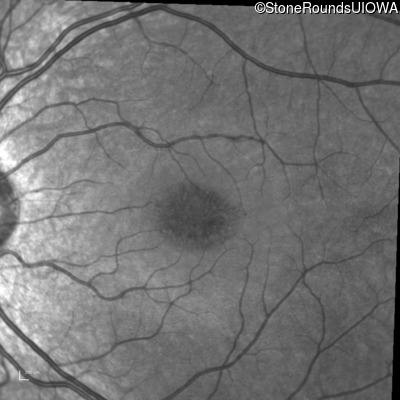

Infrared Fundus Photograph - Left - 20/40 +2

Exemplar